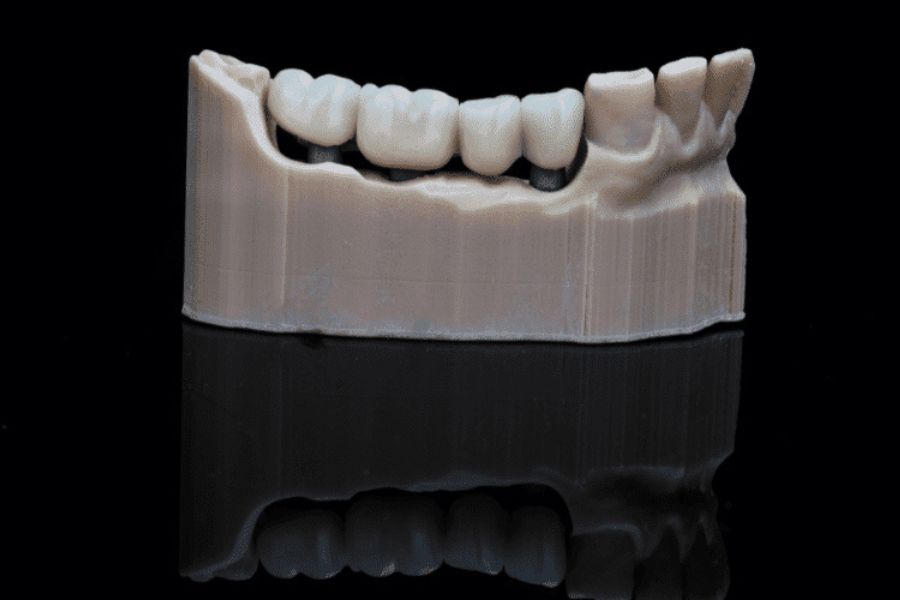

Mô hình cầu răng sứ trên Implant

Cầu răng sứ bị hở gây mất thẩm mỹ nụ cười, tăng nguy cơ sâu răng và viêm nha chu, đau nhức kéo dài, hôi miệng, nguy cơ mất răng trụ, và ảnh hưởng tiêu cực đến hệ tiêu hóa do khó nhai.